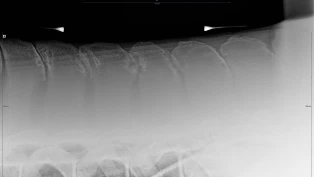

Trakk alle fortennene: – Nå er Mellis er full av liv igjen

8. november 2025, 09:00

Kristin Løkvik Knudsen (37) har fått en lykkeligere hest etter at Mellis fikk trukket alle fortennene. Det er ikke alltid enkelt å oppdage sykdommen EOTRH, forteller hesteodontolog Linn-Anett Hillestad. – Hester spiser selv om de har vondt i munnen, sier hun.